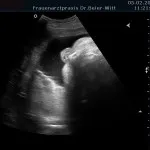

Frühschwangerschaft:

Ultraschall_17